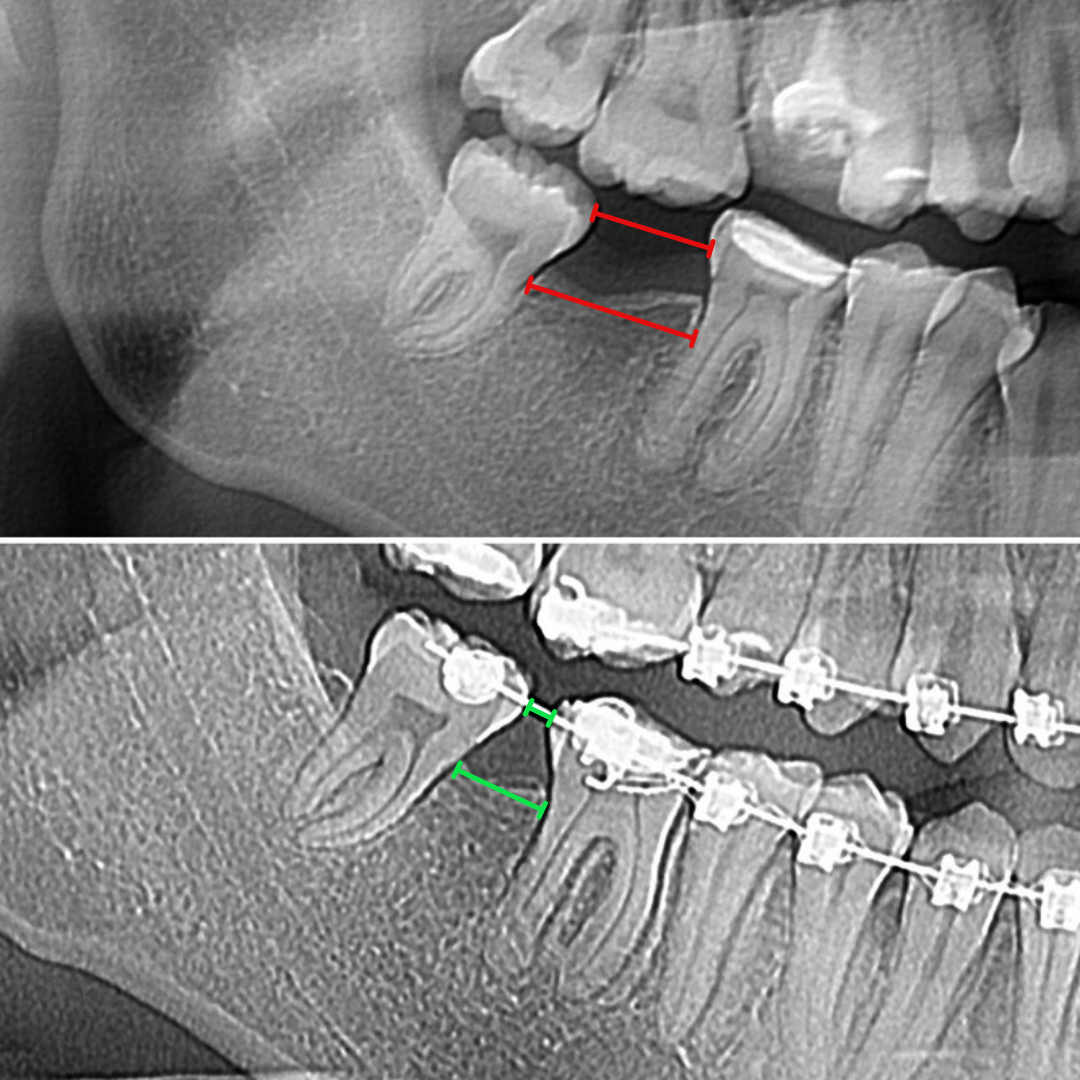

🦷 8-е зубы или зубы "мудрости" обычно прорезываются позже всех остальных зубов, где-то в 15-25 лет. Этот факт даёт им шанс дольше оставаться здоровыми.

✅ В этом клиническом примере 6-е зубы оказались разрушенными, а 7-ой и вовсе удален (на рентгеновском снимке снизу слева). А вот зубы "мудрости" оказались вполне себе хорошими! Решили замещать "мертвые" зубы "живыми", а снизу слева перемещать 8-ой на место удаленного 7-ого и таким образом избежать протезирования!